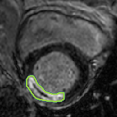

4.2 Visual assessment

We select the case that achieves the highest and lowest dice score for visual assessment. Fig. 4 shows example segmentation results where the proposed method achieved the highest agreement with the ground truth delineations. Fig. 5 shows example segmentation results where the proposed method achieved the lowest agreement with the ground truth delineations.